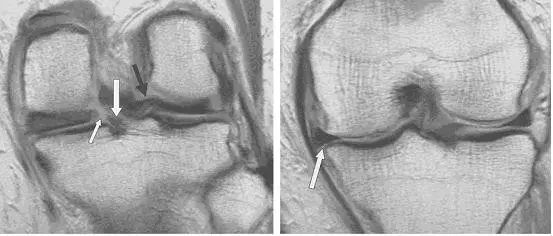

图 13 横行撕裂与半月板囊肿

T2像中可看到明亮的囊肿(红色箭头)和水平走形的线形高信号(蓝色箭头)。半月板囊肿是由于半月板撕裂后组织液聚集在关节腔形成。是否有半月板囊肿对手术入路的选择有重要影响。

图 14 半月板根部撕裂和半月板膨出

左图:冠状面可见内侧半月板后角在与根部(与胫骨连接的部位,白色大箭头)交接的部位有一个全层的撕裂(白色小箭头),可与对侧正常结构对比(黑色箭头)。右图:冠状面可见内侧半月板体部膨出关节(白色箭头),半跨与胫骨平台上。本图还可看到内侧股骨髁的关节软骨有相较于外侧的退行性缺失。